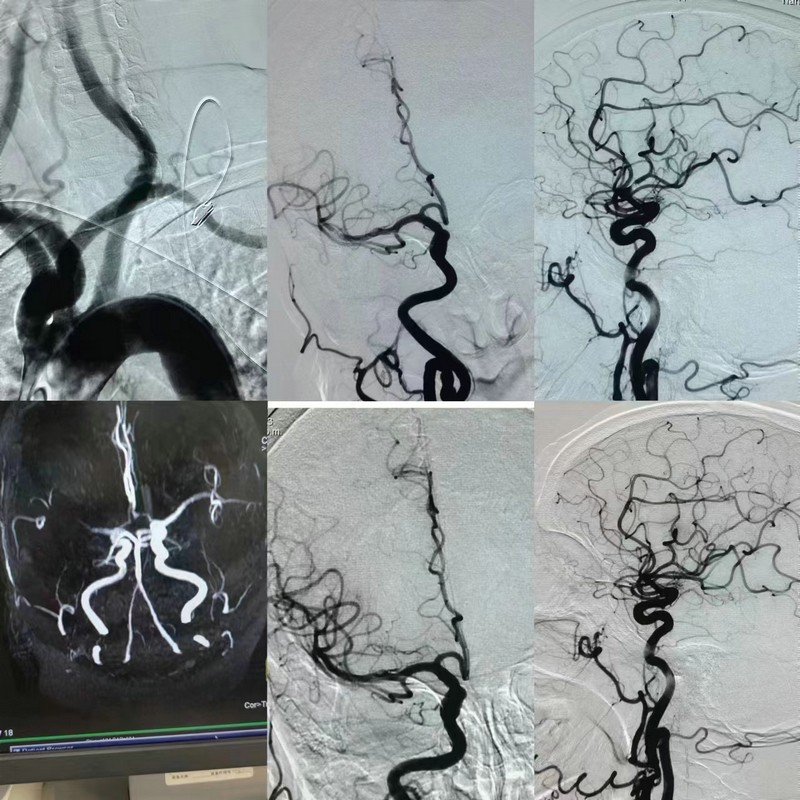

患者到達核磁室后,立刻安排了頭顱MR檢查,很快,李醫(yī)生在現(xiàn)場已經(jīng)做出了判斷,患者向右凝視,左側(cè)肢體偏癱,右側(cè)大腦中動脈閉塞,他沉著冷靜的向檢查室外焦急等待的家屬簡明扼要的告知了病情“病人情況非常危險,好在剛剛發(fā)病,我們有很好治療手段,可以溶栓并且橋接機械取栓治療,家屬同意我們馬上執(zhí)行……”。家屬聽后表示同意并會積極配合。李醫(yī)生電話報告科主任的同時也通知病房護士,告知患者體重,準備溶栓,說完后和家屬一起推著平車向病房奔去,到達病房時,值班護士已準備好一切,大家分工合作,李醫(yī)生再次談話并簽字,口頭下達醫(yī)囑,所有程序緊張有序的進行,溶栓藥物順利的發(fā)揮作用,可大家仍然沒有松懈,患者高齡,大動脈閉塞,隨時可能出現(xiàn)危機情況,科主任馬志恒和寧醫(yī)生守在患者床旁,密切的關(guān)注著病情變化,李醫(yī)生聯(lián)系腦血管介入中心及導管室,其他醫(yī)護人員開始做術(shù)前準備。很快,介入導管室醫(yī)務(wù)人員已就位,患者被護送至導管室,進行橋接治療……40 分鐘后,電話再次響起,“患者溶栓藥物獲益,大腦中動脈血流已恢復,遠端逃逸的微栓子已行血管內(nèi)治療,患者入院前癥狀完全消失!甭牭竭@個消息,所有人都如釋重負,剛才奔走中的汗水和緊張在這一刻消失殆盡,家屬激動的熱淚盈眶。

馬志恒主任介紹說:“靜脈溶栓治療即通過具有血栓溶解作用的藥物,達到溶解血栓的目的。對于癥狀出現(xiàn)6小時內(nèi)的急性腦梗病人,靜脈溶栓治療是首選治療方案,對于約40%急性腦梗病人在接受靜脈溶栓過程中癥狀能得到明顯改善。但有些患者即便是應用靜脈溶栓治療,病情仍有可能進一步發(fā)展,這與患者的血管基礎(chǔ)、身體條件有關(guān),需要在靜脈溶栓的同時快速啟動血管內(nèi)介入治療,開通血管。這位老人就是溶栓獲益后啟動血管內(nèi)介入治療,才讓微栓子無所遁形,將其一網(wǎng)打盡,才有了后期這么好的效果。馬志恒還說:當身邊有人突然出現(xiàn)如“頭暈、頭痛、視物模糊、言語不清、肢體無力、感覺異常”等癥狀時,一定要引起重視,這很有可能是“腦卒中”,應盡快撥打120到有卒中中心的醫(yī)院,一定要在最短的時間內(nèi)前往醫(yī)院救治,這樣才能最大程度的為患者爭取更多的救治時間。